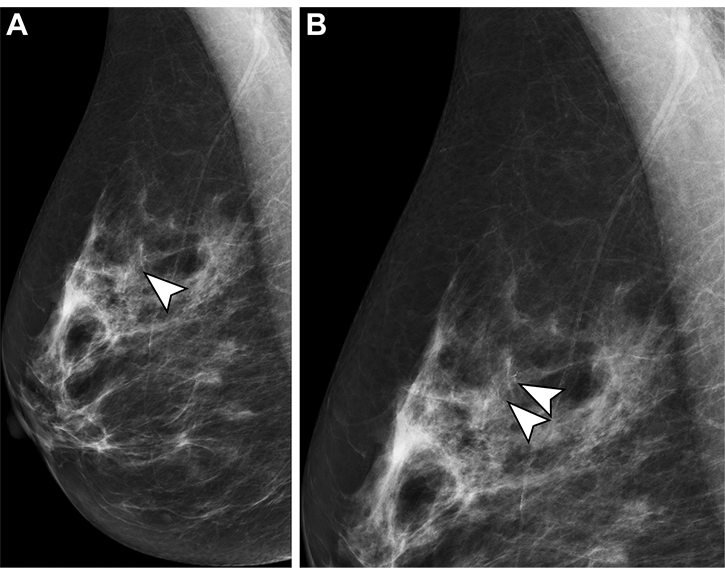

Mammograms in a 54-year-old woman undergoing her second screening mammographic examination. (A) There are 15 mm of pleomorphic microcalcifications (arrowhead) in the superior right breast on the mediolateral oblique view. (B) The microcalcifications (arrowheads) are best observed on this magnified view. It was not recalled by the radiographer who read the mammogram first and was recalled by the radiologist who read the image second. Stereotactic-guided biopsy showed high-grade ductal carcinoma in situ.